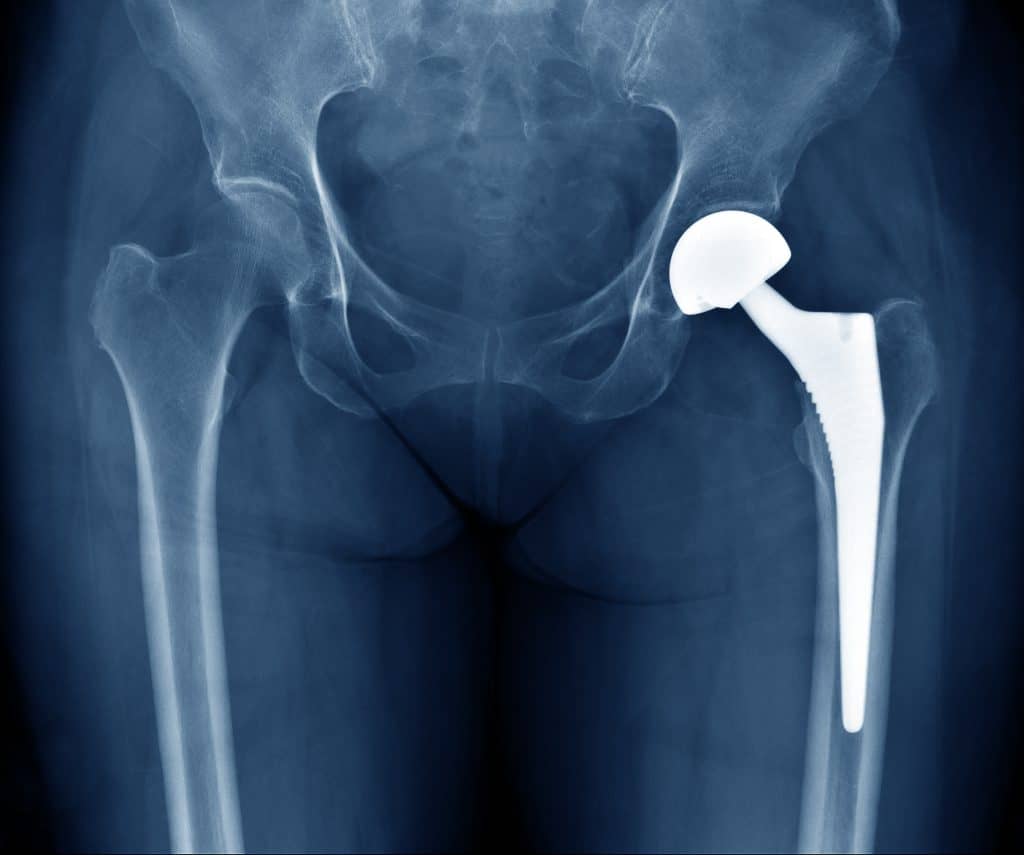

Uma descoberta particularmente útil em um país onde são feitas mais de 85.000 substituições de quadril e joelho anualmente – seja pelo envelhecimento da população, lesões esportivas ou efeitos da obesidade.